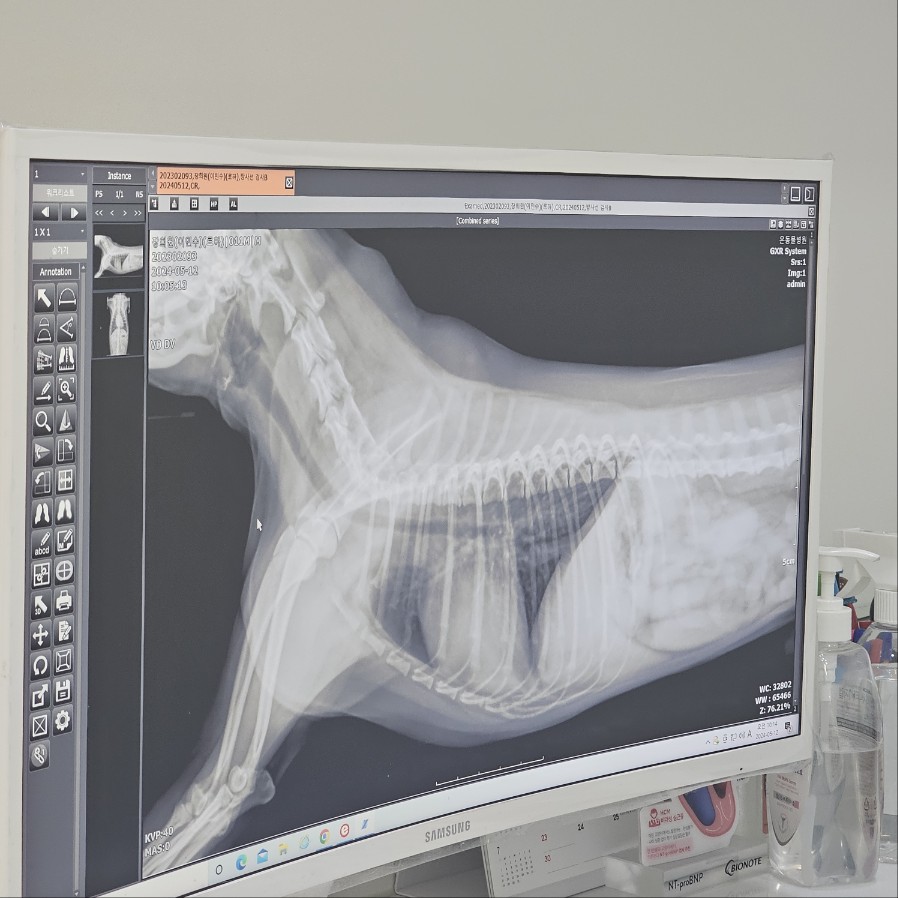

강아지도-꿈을-꾸나요 잠자는 경우에 강아지 호흡이 빨라지는 원인은 강아지가 꿈을 꾸기 때문일 수도 있습니다. 실제로 우리 강아지 '로하'가 3일 전부터 참을 잘 때, 호흡수가 1분에 60회 정도 해서 너무 놀라 병원에 간 적이 있었는데요. 수의사 선생님께서 X-ray를 찍어보자 하셔서 찍은 결과 아무 이상이 없었습니다. 그래서 해주시는 말씀이 강아지가 얕은 잠을 자는 경우에는 꿈을 꾸는 것일 수도 있다고 하셨습니다. 로하는 평소에는 호흡수가 안정적인데 잠에 들고 5분 정도 지난 후부터 호흡수가 빨라졌거든요. 또한, 이때 발을 움직이기도 하고 가끔 '멍' 하는 것을 봐서는 꿈을 꾸는 것인가 봅니다.

강아지-엑스레이 그 외에는 X-ray를 찍어봐야 알 수 있지만, 폐에 물이 차서 호흡이 어려워지는 폐수종 증상이 있을 수도 있고, 심장에 문제가 있을 수도 있습니다. 보호자는 강아지가 잠을 잘 때, 평소에 호흡수가 빨라졌는지 영상을 촬영하셔서 가까운 동물 병원에 방문하여 정밀 검사를 받아보아야 합니다.